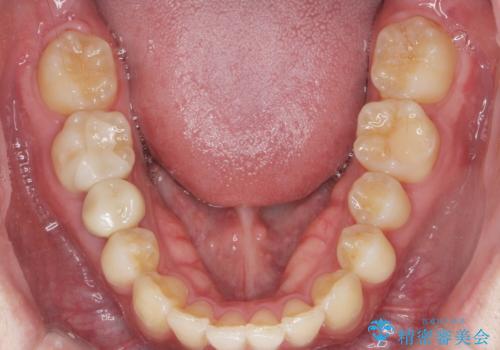

前歯のがたつきをなおしたい マウスピース矯正

- 気になる前歯のがたつきをきれいにしたい。と矯正治療を希望され来院されました。

大きな歯列の乱れはないため、倒れ込んでいる奥歯の傾きの改善、前歯のがたつきを改善する治療を計画します。

見た目が良くなっただけではなく、歯ブラシがしやすくなった!と治療後の歯並びに喜んでいただくことができました。